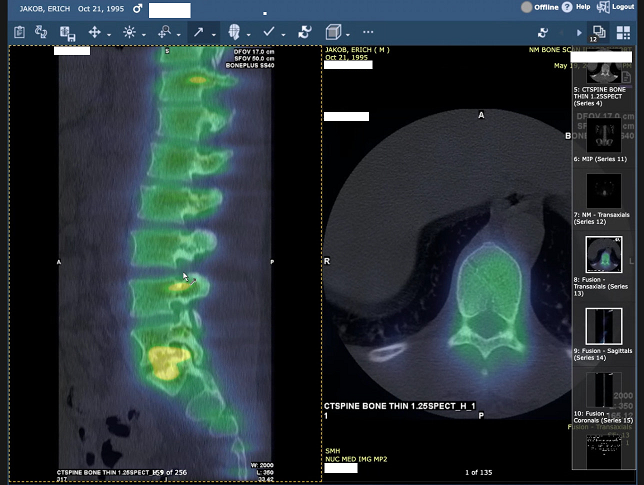

Erich is 29 and has been living with constant, debilitating pain from severe spinal damage. His condition has progressed so much that he can’t sit upright, struggles to sleep, and is mostly confined to bed. It’s been heartbreaking to watch someone I love lose access to the simple things that make life feel normal. Going outside, seeing friends, even standing long enough to cook a meal all have become excruciating.

Over the past several months, Erich has already spent thousands of dollars out of pocket on physical therapy, nerve studies, epidural injections, medications, and consultations with specialists. Despite following every conservative treatment step doctors recommended, his insurance has continued to deny the one procedure multiple spine surgeons agree could provide meaningful relief: artificial disc replacement surgery. These denials don’t reflect the reality of his condition or his treatment history. With every month that passes, his pain worsens and his need for surgery grows more urgent.